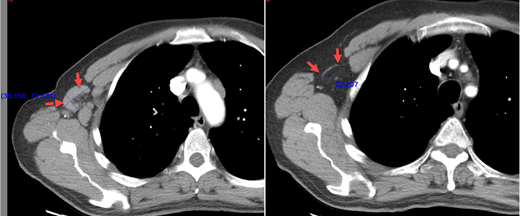

Background: IWCLL 2008 and 2018 criteria require that all lymph nodes/nodal masses be ≤ 15mm in longest diameter (LDi) to be consistent with a CR. Lymph nodes or nodal masses >15mm in the LDi are considered abnormal. However, it has been observed that some bulky nodes may become thin and streak-like on follow-up timepoints (Figure 1) and may be normal by clinical and imaging standards (<10mm in short axis diameter) (Cheson et al Journal of Clinical Oncology, 17:1244, 1999) however, they continue to be >15mm in LDi (LDi Positive nodes- LDi+) and, hence, categorized as abnormal per iwCLL criteria. In lymphoma studies, FDG-PET negativity is the driver of CR, and residual disease on CT scan is allowed for CR. However, in the iwCLL response assessment, LDi+ nodes may prevent a true CR.

Figure 1: A large right axillary node at baseline (image on left), is reduced in size and is thin, streak like (image on right) but is abnormal as per iwCLL criteria by LDi definition.